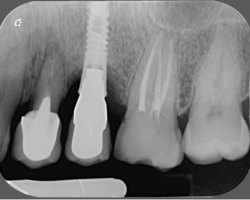

Bone level or Tissue level

S’il est vrai, que pour des raisons de contamination bactérienne, notamment au niveau des micro joints des implants, il est conseillé de mettre ce micro-joint à l’extérieur du niveau osseux, et que le fait d’avoir un col lisse qui place ce micro-joint au-dessus des tissus, l’adhésion des tissus à la surface titane de l’implant est très bonne.

Cependant, on aperçoit également des péri-implantites sur des tissues levels…

On privilégiera donc un implant avec une connexion interne pseudo cône morse, plutôt rugueux (modéré) pour améliorer l’ostéointégration et avec un col lisse plus ou moins important pour la stabilité des tissus et positionner le micro-joint en dehors de l’os.